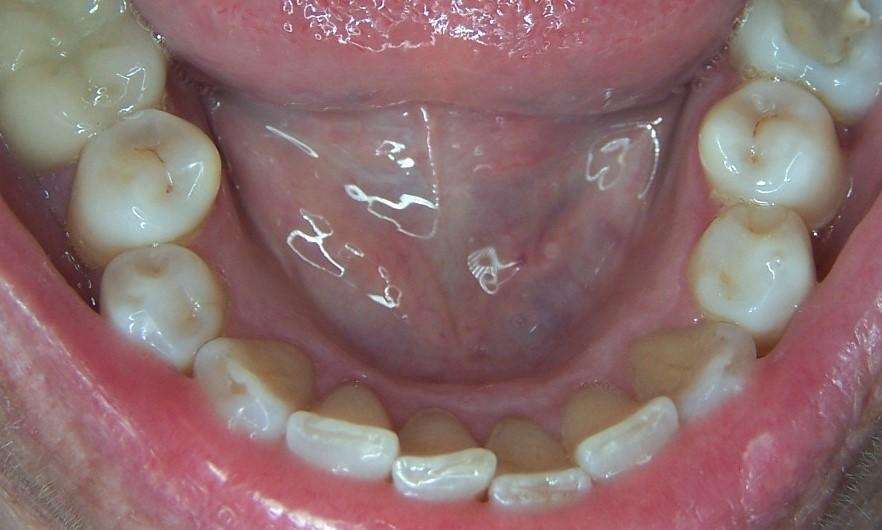

A long time patient of ours had noticed her teeth shifting and her bite changing. She noticed that her front teeth were colliding more than they used to which could be causing some chipping of her bottom teeth. As well, her bottom teeth were crowded and hard to floss. We suggested clear aligners in Los Gatos as a service to improve the function and health of her gums.

As a very compliant patient, the clear aligner process took about 10 months. After completion, our patient felt that her teeth were straighter, and had a more balanced and softer bite. She also started flossing more regularly because it was much easier to do now, which has led to improved gum health.